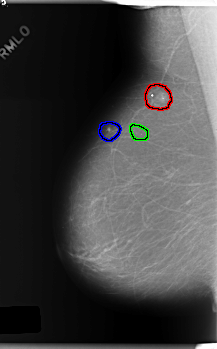

C_0236_1.RIGHT_MLO

RIGHT_MLO LINES 5920 PIXELS_PER_LINE 3688 BITS_PER_PIXEL 12 RESOLUTION 50 OVERLAY

FILE: C_0236_1.RIGHT_MLO.OVERLAY

TOTAL_ABNORMALITIES 3

ABNORMALITY 1

LESION_TYPE CALCIFICATION TYPE FINE_LINEAR_BRANCHING DISTRIBUTION CLUSTERED

LESION_TYPE MASS SHAPE IRREGULAR MARGINS ILL_DEFINED

ASSESSMENT 4

SUBTLETY 5

PATHOLOGY BENIGN

ABNORMALITY 2

LESION_TYPE CALCIFICATION TYPE PUNCTATE DISTRIBUTION CLUSTERED

ABNORMALITY 3

LESION_TYPE CALCIFICATION TYPE PLEOMORPHIC DISTRIBUTION CLUSTERED